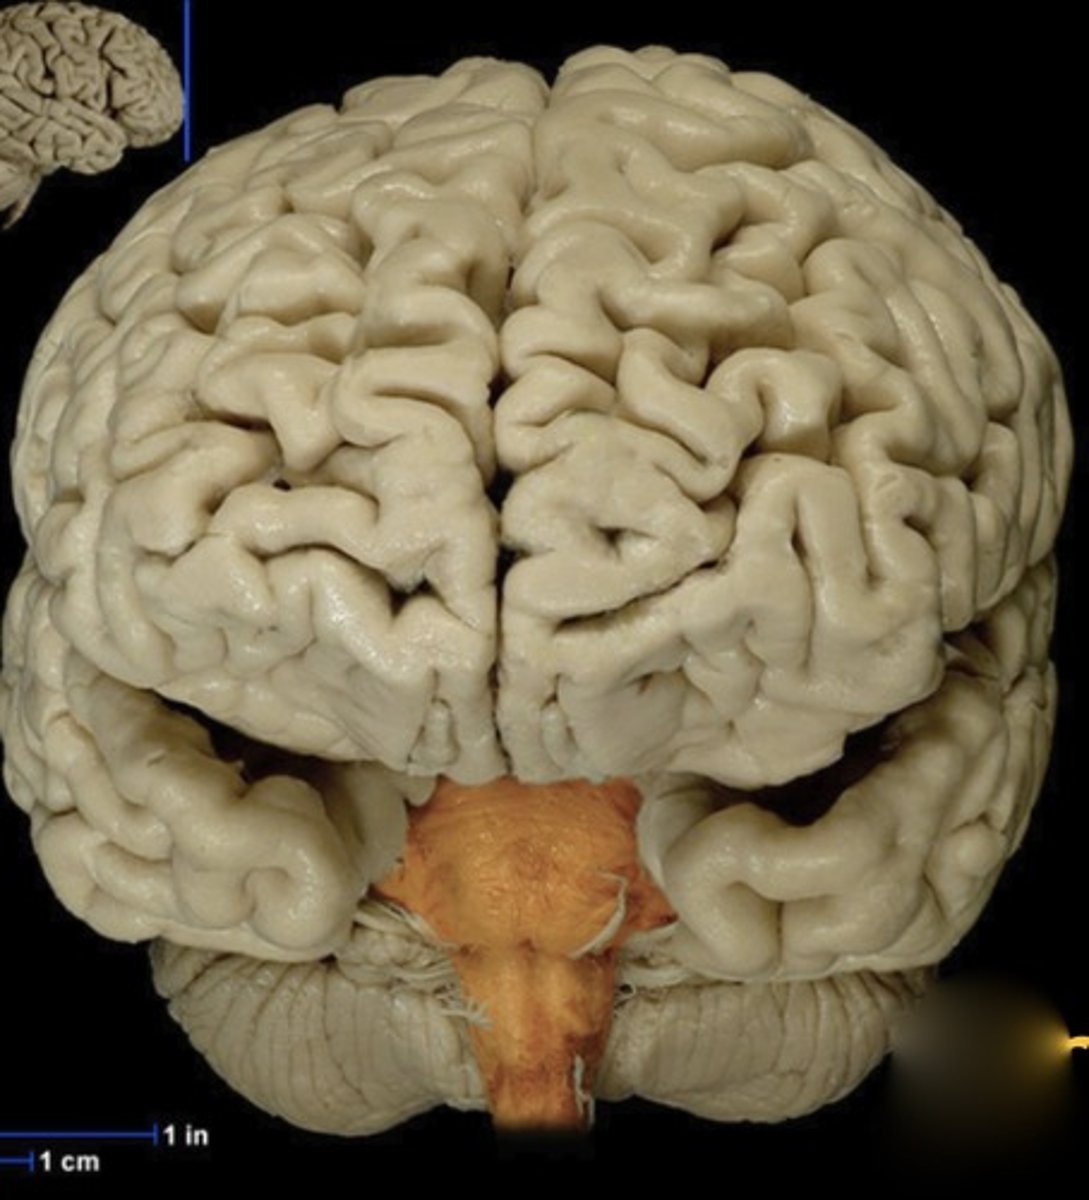

Cerebrum

Name this structure

Longitudinal fissure

Name this structure

Brainstem

Name this structure